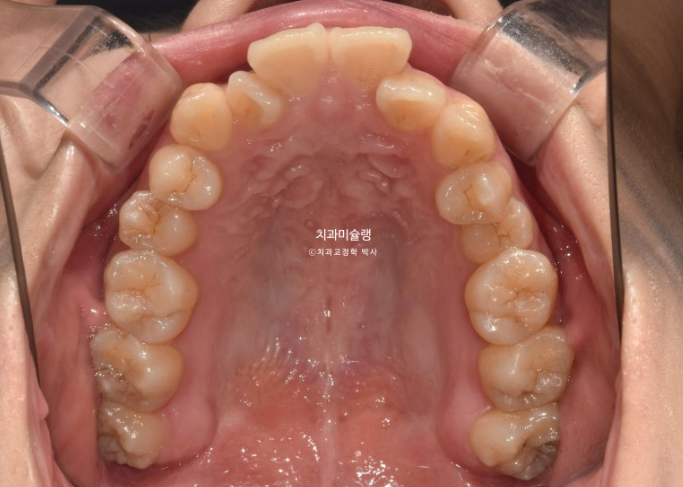

23년 10월 교정치료를 이해 온 30대 환자분입니다.

약 2mm 정도의 중심선 불일치 그리고 덧니가 보입니다.

개방교합도 있고

30년간 공간이 없어서 미처 내려오지 못한 작은어금니도 있습니다.

덧니가 워낙 심해 작은어금니 4개 발치가 불가피한 상황입니다.

첫 세트 장치는 56개이고 7일이 하나씩 장치를 교체했습니다.